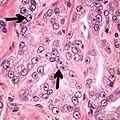

- Intraductal carcinoma of the prostate with an infiltrative growth pattern may be morphologically difficult to distinguish from invasive cancer. One focus shows comedonecrosis (arrow), morphologically suggesting Gleason pattern 5 invasive carcinoma (a haematoxylin and eosin, b CK5/6)[19]

- Intraductal carcinoma of the prostate with very patchy basal cells identified by immunohistochemistry. At least some of the glands lacking basal cell immunoreactivity represent intraductal rather than invasive carcinoma (a haematoxylin and eosin, b CK 5/6)[19]